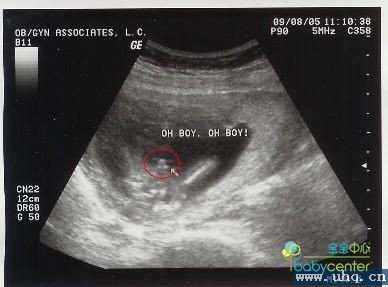

B超图宝宝下身的3个白点是男孩的生殖器吗? 无意间发现16周的B超图上,宝宝的下身有3个白点。跟网上看来男孩子的B超图样子很像,所以想请教一下看得懂的人帮我确认一下。这张是我自己的,圈起来的地方有3个呈三角形的白点,图片拍的不是很清楚。这张是网上看来的,他们的照的比较特写老家思想还是倾向于男孩子,但是我个人男孩女孩都是自己的,要是男孩子的话就更好了。虽然还有两个多月就要生了,但是还是很想知道我自己的这个发现对不对,谢谢各位了。 点击展开 匿名用户 2014-02-11 16:00 满意回答 您好,是的,如果宝宝的姿势和下面图一致就可以确定无疑。 匿名用户 2018-01-13 01:54 宝宝知道提示您:回答为网友贡献,仅供参考。 相关问题 男宝宝的b超图真的是显示有一个白点的地方就是男宝宝吗? 昨天去做B超了,看见胎儿裤裆里有个白点说是男孩,准吗?女孩什么样啊? 今天早上去照B超,25周+,医生说胎儿生殖器那里只看到有一点,这样子的话是男宝宝还是女宝宝呢?好好奇喔…

无意间发现16周的B超图上,宝宝的下身有3个白点。跟网上看来男孩子的B超图样子很像,所以想请教一下看得懂的人帮我确认一下。这张是我自己的,圈起来的地方有3个呈三角形的白点,图片拍的不是很清楚。这张是网上看来的,他们的照的比较特写老家思想还是倾向于男孩子,但是我个人男孩女孩都是自己的,要是男孩子的话就更好了。虽然还有两个多月就要生了,但是还是很想知道我自己的这个发现对不对,谢谢各位了。